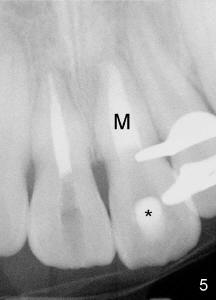

10. Take a wet cotton pellet, remove excess moisture from the pellet and place in the canal.  Seal the access preparation with a temporary restoration (Fig.5: *) for a minimum of four hours